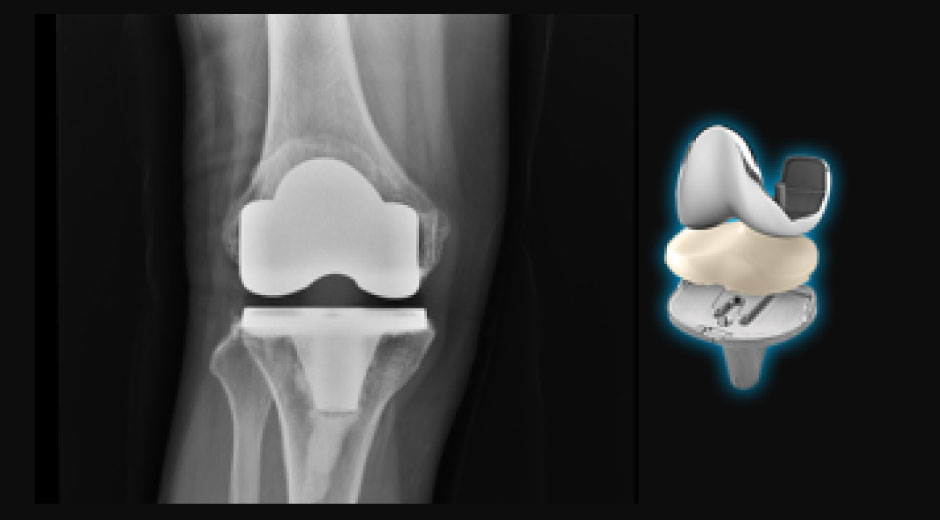

人工関節手術

股関節・膝関節 人工関節 手術

股関節・膝関節の手術においては、骨折固定術、人工関節置換術、靭帯再建術、骨切り術などを行い、術中はもちろん、術後の痛みも取り除く神経ブロックの併用例も豊富です。また、関節外科・スポーツ整形外科の専門医による関節鏡視下手術にも対応しております。